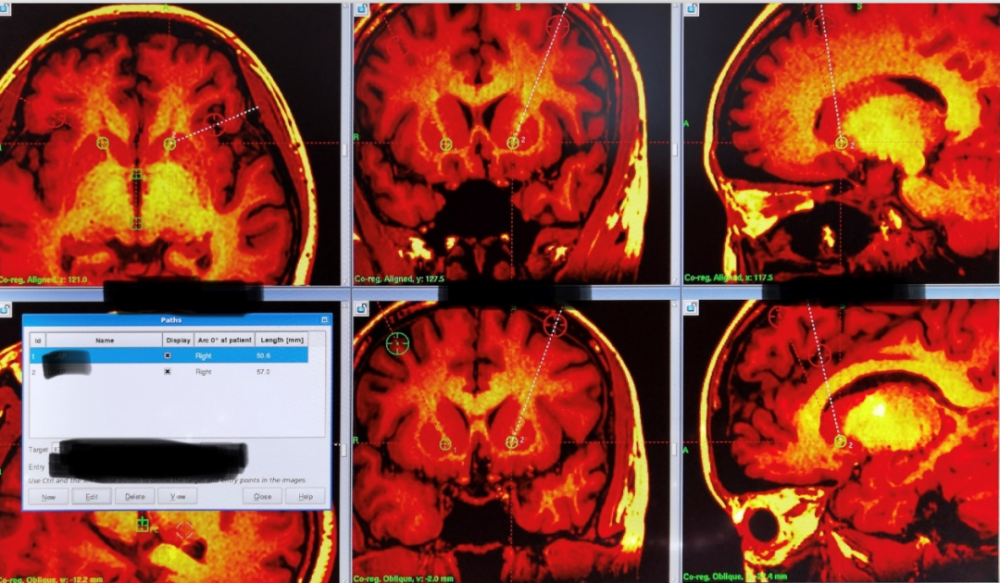

11月15日,在头部立体定向定位技术辅助下,通过头部不到2cm的微创切口,易伟教授团队将直径约为1mm 的电极,置入颅内相应神经核团靶点,为小张成功实施了脑深部电刺激手术。

易伟教授介绍,强迫症的发生与脑内的皮质-纹状体-丘脑-皮质环路密切相关。采用微创可调节的脑深部电刺激术,对相关神经环路进行调节和整合,可纠正异常的神经环路功能,达到治疗疾病的目的。

在立体定向导航系统支持下,医生能精确找到相应神经核团进行调控,同时有效避开大脑中的重要神经和血管,避免损伤大脑运动、认知及语言功能区,从而规避偏瘫、失语、认知功能损害等手术后遗症。